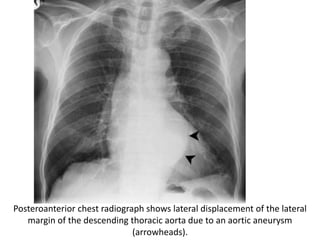

Posteroanterior chest radiograph shows lateral displacement of the lateral

margin of the descending thoracic aorta due to an aortic aneurysm

(arrowheads).

CT scan also demonstrates the aneurysm (arrow).

Posteroanterior chest radiographshows lateral displacement of the lateral margin of the descending thoracic aorta due to an aortic aneurysm (arrowheads).

CT scan alsodemonstrates the aneurysm (arrow).